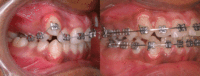

What kind of "braces" will you need?

Custom-made orthodontic appliances or "braces" are chosen according to the problems being treated and lifestyle of patient being treated. They may be "removable" or "fixed" (temporarily cemented in place). They may be made of metal, plastic or both. All appliances will create gentle pressure and cause teeth to move into their proper positions. Under this pressure the body builds up new tissue to support the improved position of the teeth.

A correct appliance, custom fitted into place, does not harm the teeth. Before orthodontic treatment starts, all cavities must be filled. During orthodontic treatment, you must brush your teeth regularly and avoid those foods discouraged by the doctor.